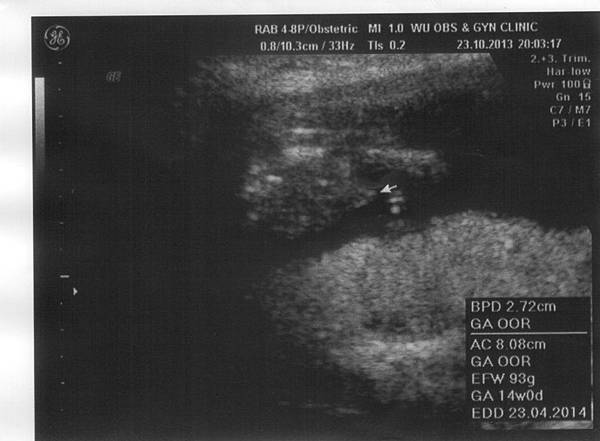

• 決定是你了!小馬哥!

14w0d-116w6d-115w2d-115w2d-216w6d-1